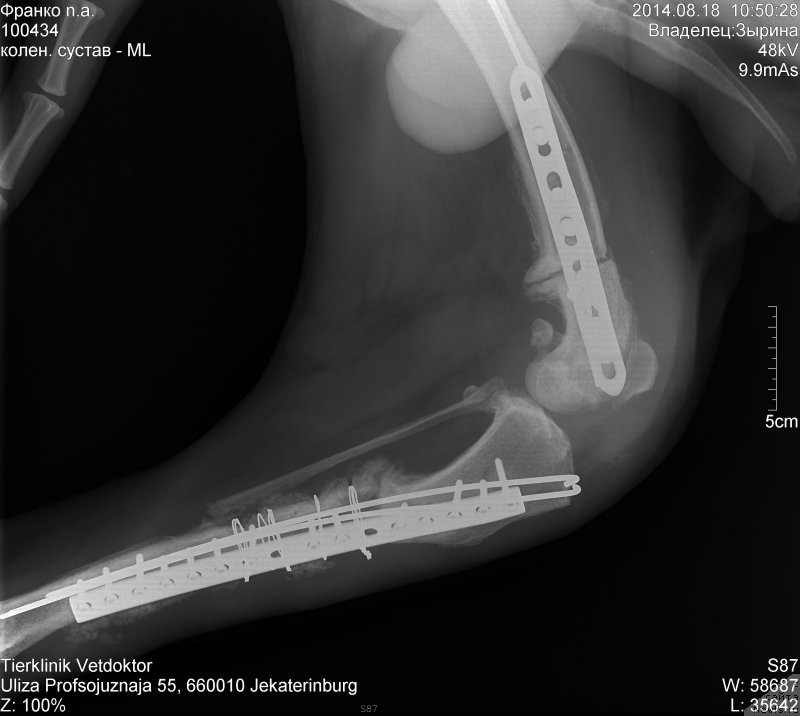

Снимок на почте у Лены.

Сейчас позвонил врач сказал что одна кость размыта. Остиемиелит лечится внутриартериальным введением антибиотика в бедренную кость.как то так.

Но это надо делать быстро пока не поздно.

Кто то может еще снимки показать?

Может человеческим рентгенологам

Фотография № 161323

Леночка посмотрела снимок и отправила кому смогла.

Но я совсем запуталась.... Там где проволочка это же низ лапы, кость на снимке размытая, а там ты писала, все нормально, а гнойный свищ сверху, а на рентгене кость нормальная, лучше чем внизу.

Ленуль, напиши что говорит и пишет Сергей Александрович и другие врачи и как комментируют этот снимок. Где все же этот гнойный очаг и от чего он?

Источник гноя не установлен. Он в области колена где проволока.

Вечером позвонил врач сказал что дело плохо.Нет костных мозолей и подтверждает плохой диагноз.